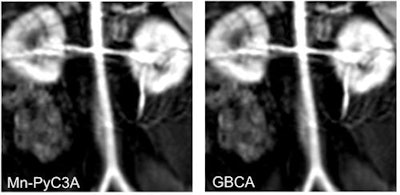

In their most recent study, the researchers separately compared the efficacy and image quality of Mn-PyC3A against gadoteric acid (Dotarem, Guerbet) to detect breast cancer tumors and against gadoxetate disodium (Eovist, Bayer HealthCare) to identify metastatic liver disease in rodent models (Investigative Radiology, November 2019, Vol. 54:11, pp. 697-703). The second objective was to see how well Mn-PyC3A and the two GBCAs were excreted from the rodents' bodies over the course of seven days.

In evaluating the results, the researchers found that Mn-PyC3A achieved greater contrast-to-noise ratios in comparisons with both GBCAs to provide sufficiently adequate image quality for both the breast and liver. In addition, after one day, the percentage of injected dose of manganese still remaining in the rodents' systems (0.32 ± 0.2) was significantly less than that of gadolinium (0.57 ± 0.12) (p = 0.003). After seven days, the percentage of leftover manganese (0.058 ± 0.051) in the rodents again was significantly less than the percentage of residual gadolinium (0.19 ± 0.052) (p < 0.0001).

Caravan and his colleagues also reported similar success in a November 2017 study that concluded that the MBCA was equivalent to gadolinium-based contrast for enhancement of a baboon's blood vessels. Mn-PyC3A also was quickly excreted through both kidney and liver clearance, leaving no evidence of the release of "free manganese" in these subjects.